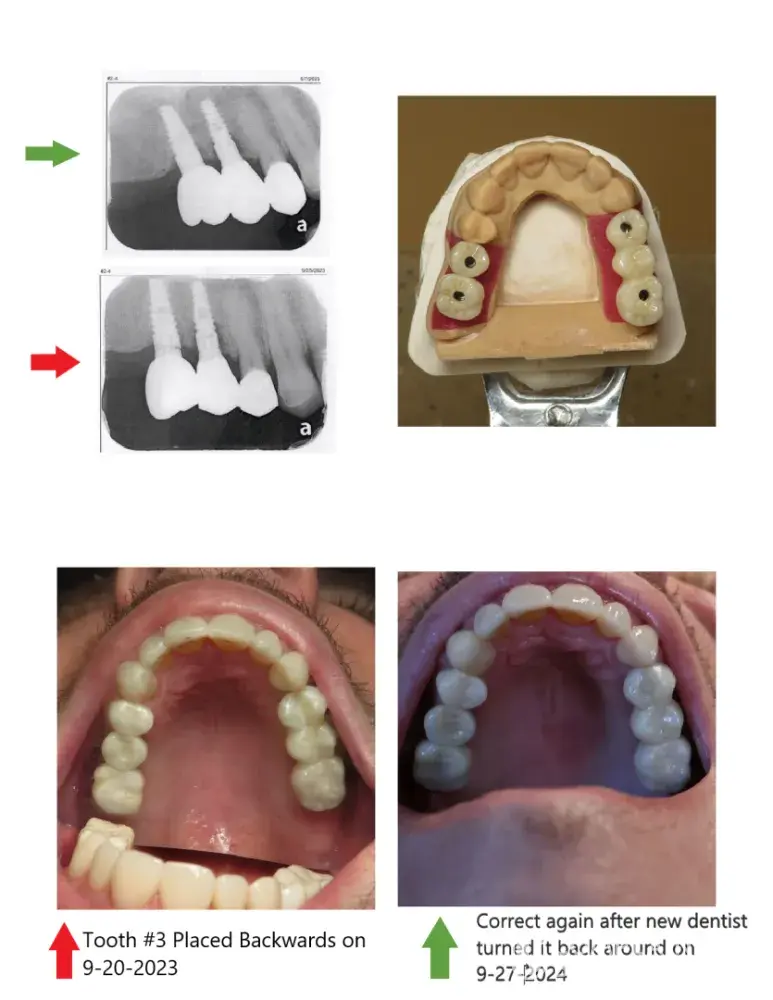

Grandville Dental Health Center PC - Full mouth restoration - dental crowns & bridges

I've spent over $50,000 on a full mouth restoration through Grandville Dental Health Center plus another $4,000 figuring out issues and it took over a year but I found out they messed up by placing a crown 180 degrees backwards and wrecked my full restoration then abandon me for no reason because they couldn't figure it out. Permanent adjustments were made...